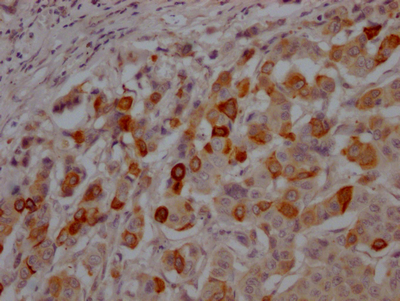

IHC image of CSB-RA216259A0HU diluted at 1:100 and staining in paraffin-embedded human breast cancer performed on a Leica BondTM system. After dewaxing and hydration, antigen retrieval was mediated by high pressure in a citrate buffer (pH 6.0). Section was blocked with 10% normal goat serum 30min at RT. Then primary antibody (1% BSA) was incubated at 4℃ overnight. The primary is detected by a Goat anti-rabbit IgG polymer labeled by HRP and visualized using 0.05% DAB.